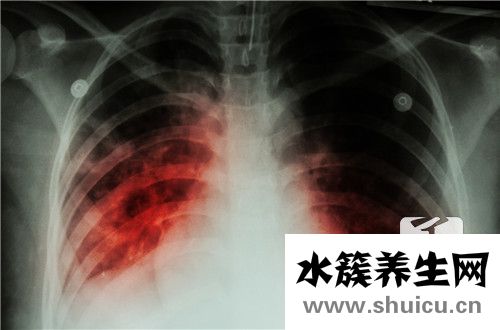

二肺紋理增多增大增厚一般是肺病或支氣管炎的要素,如彌漫性支氣管炎或肺炎。因此,雙肺紋理增多增大增厚的患者應(yīng)立即選擇抗生素治療,并可選擇X線檢查肺部疾病。根據(jù)two 肺紋理增多增大增厚的原因和...